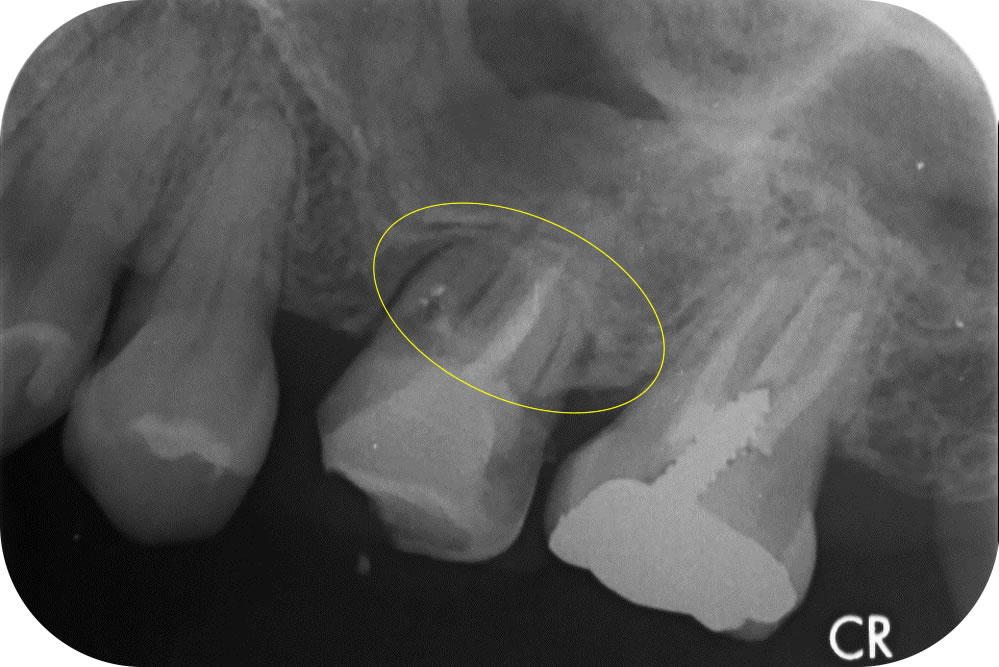

口腔内の状態を把握するため、徹底した診査・診断を行いました。この歯はまだ仮歯が装着されていましたが、根管治療は終えたとのことで、歯の根っこの部分にはお薬が詰められている状態(レントゲンで白く写ります※黄色)でした。

しかし、よく確認すると1ヶ所お薬が詰められていない根管を発見しました。このままにしておくと細菌が繁殖して、さらに症状が悪化するため、もう一度根管治療を行うことにしました。